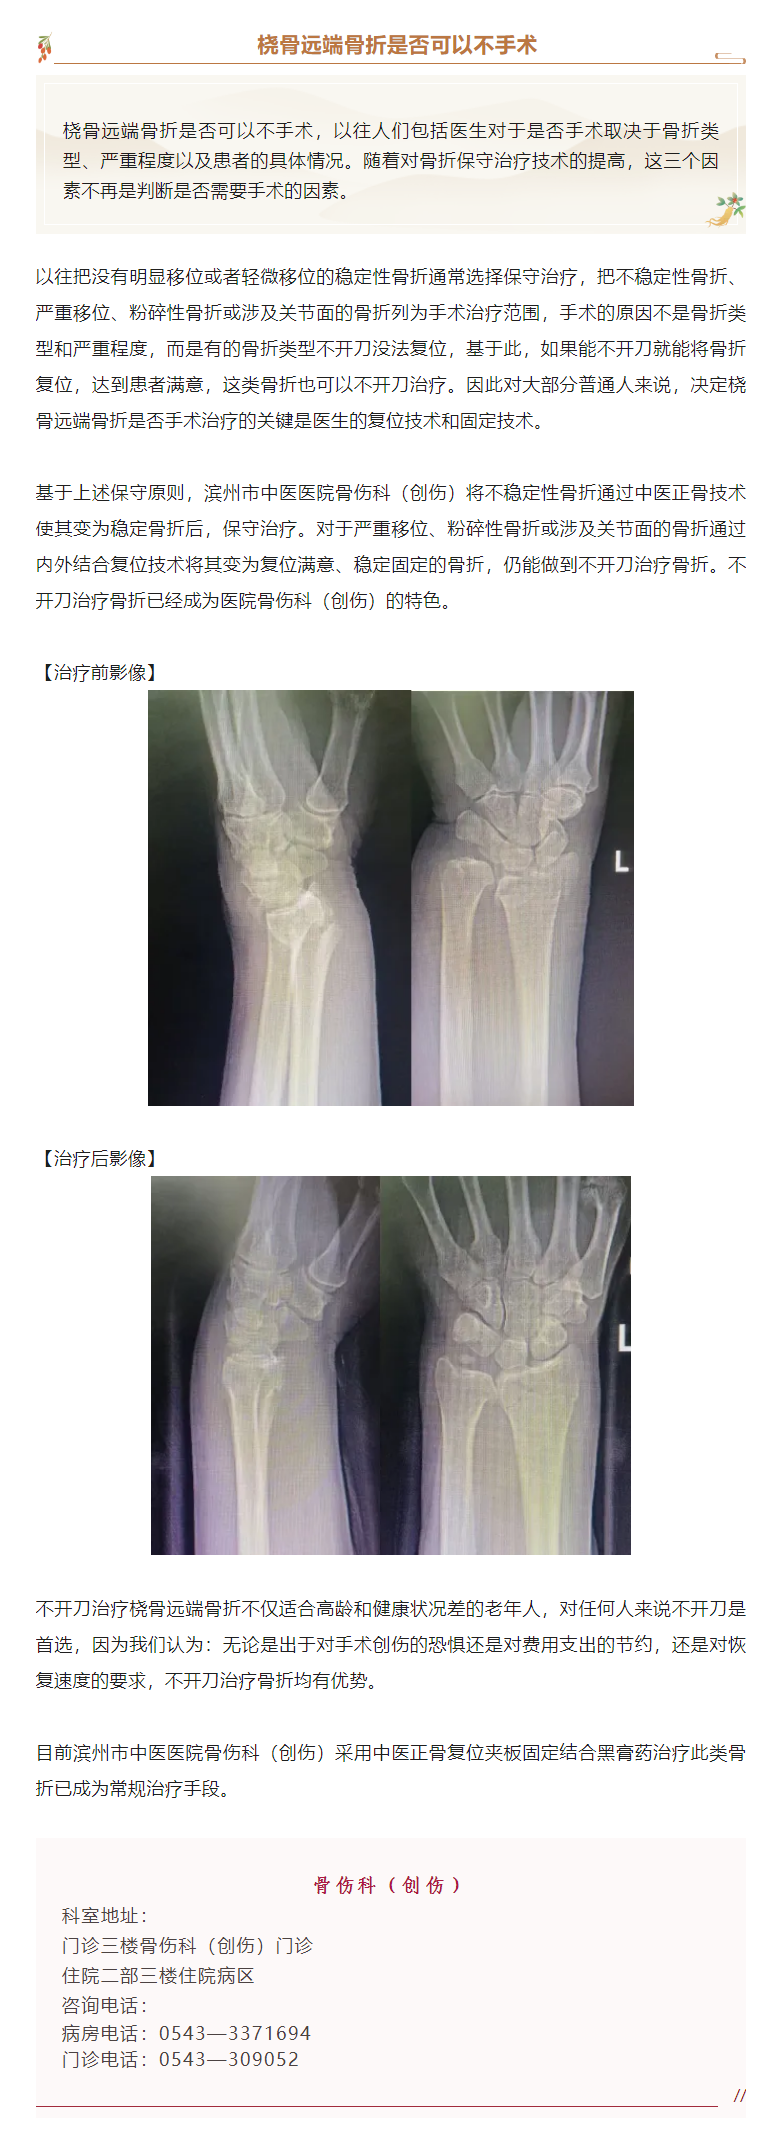

滨州市中医医院骨伤科(创伤)“不开刀”治骨折——桡骨远端骨折,能否免于手术?